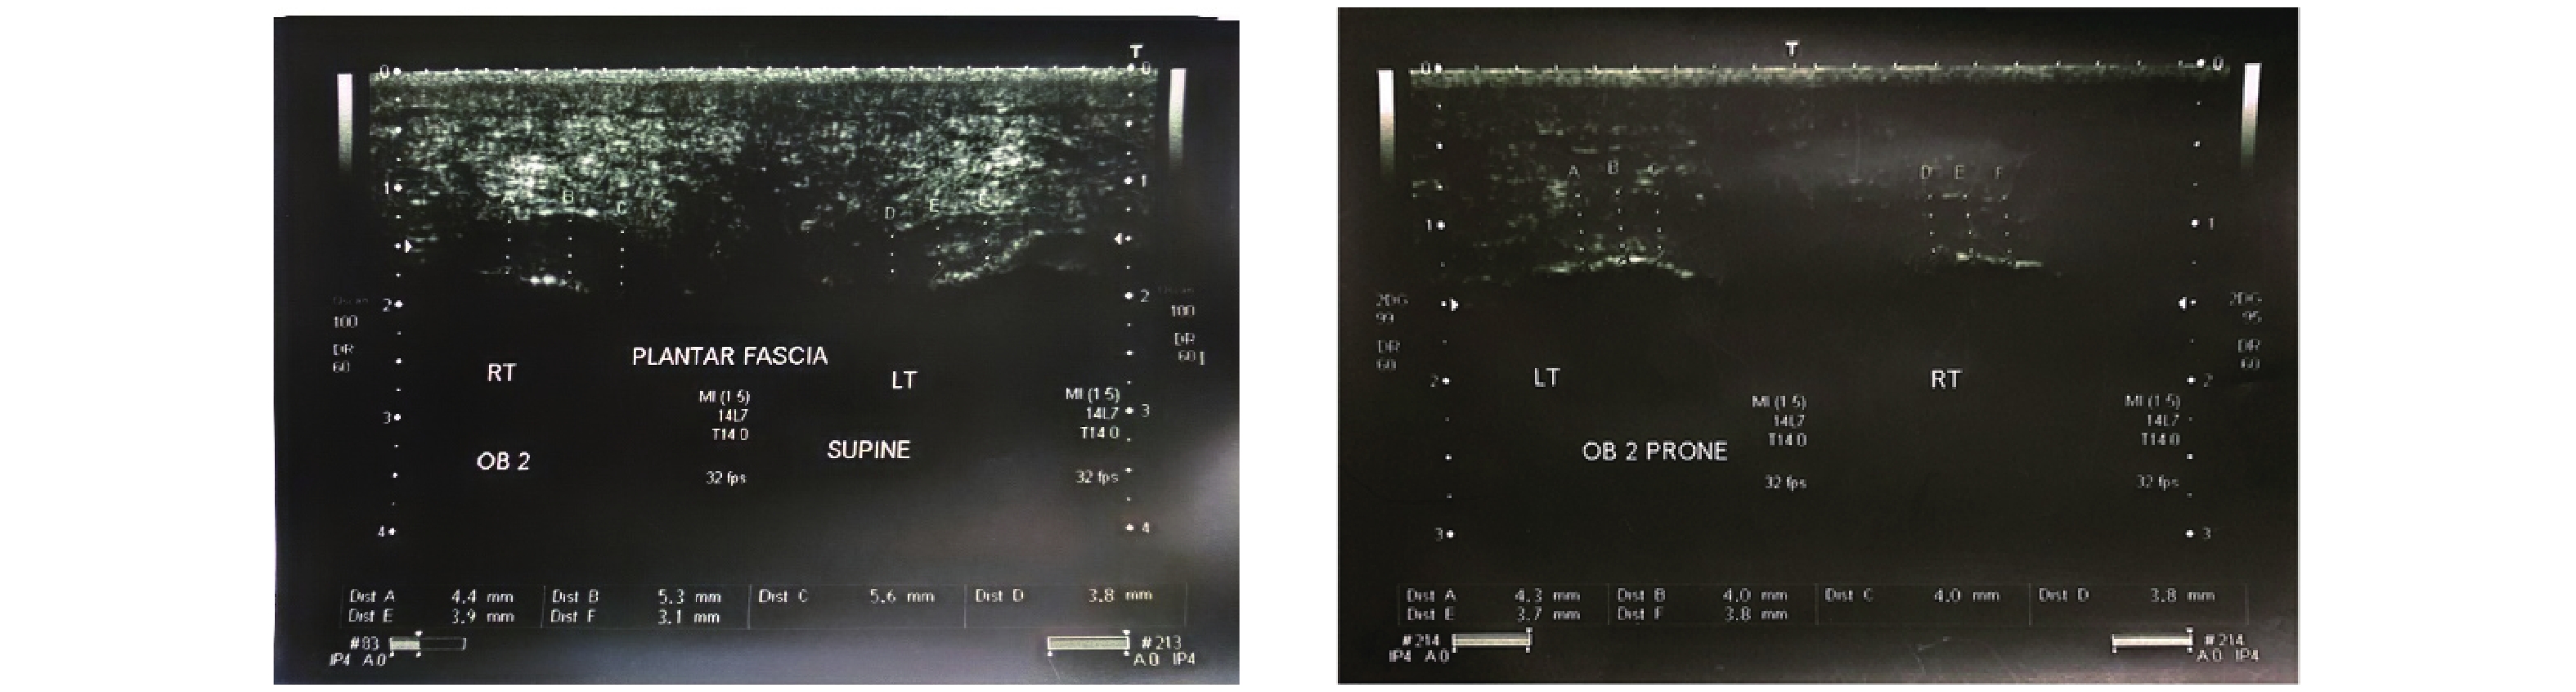

Ahn JH, Lee CW, Park C, Kim YC. Ultrasonographic examination of plantar fasciitis: a comparison of patient positions during examination. J Foot Ankle Res 2016; 9: 38.